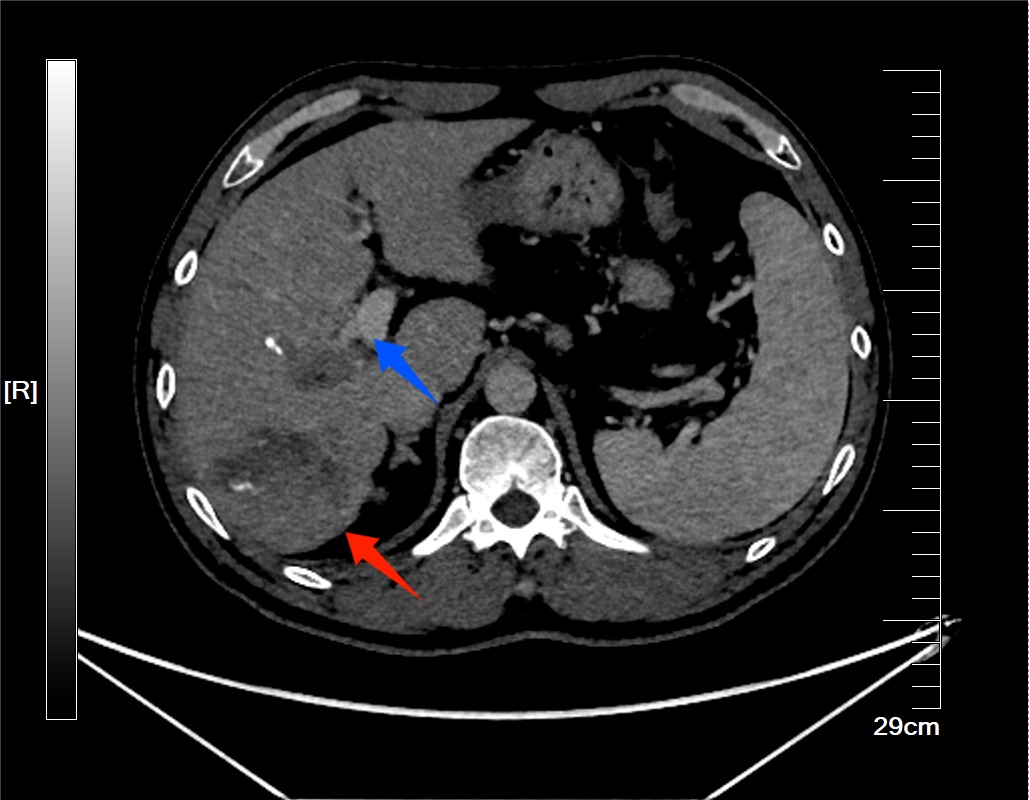

迎国庆丨治疗1个月肿瘤明显缩小!玉溪中山医院用BACE联合肝动脉栓塞介入术,逆转晚期肺癌多发转移病情

玉溪市中山医院肿瘤诊疗中心成功开展一项针对晚期肺癌多发转移的精准介入治疗:不仅为一位历经传统治疗失败的72岁患者实施支气管动脉化疗栓塞术(BACE)联合肝动脉化疗栓塞术,实现了病情的有效逆转,也为国庆节的到来献上一份特殊的礼物。72岁的毕女士在2023年10月被确诊为肺癌并骨转移。确诊后她接受了标准的一线治疗方案,并在病情稳定后进行了维持免疫治疗,延缓肿瘤进展。然而2025年3月,复查发现其肺原发病灶增大,并出现...